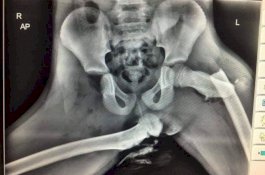

Wanita ini Suka Naikkan Kakinya di Dashboard Mobil, Begitu Kecelakaan Pinggulnya Patah